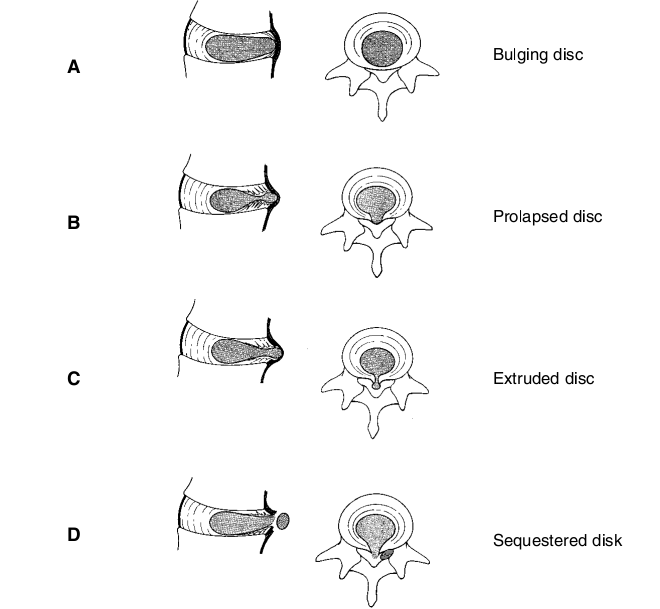

Phân loại theo liên quan với dây chằng dọc sau.

Wood chia thoát vị đĩa đệm làm 4 loại dựa trên sự tương quan giữa khối thoát vị với vòng sợi, và dây chằng dọc sau:

- Loại 1: phồng đĩa đệm (normal bulge), vòng sợi chưa bị rách hết, nhân nhày vẫn còn nằm trong vòng sợi nhưng lệch vị trí.

- Loại 2: lồi đĩa đệm hay dạng tiền thoát vị (protrusion), khối thoát vị đã xé rách vòng sợi nằm ở trước dây chằng dọc sau.

- Loại 3: thoát vị thực thụ (extrusion), khối thoát vị đã chui qua dây chằng dọc sau, nhưng còn dính liền với phần nhân nhày nằm phía trước.

- Loại 4: thoát vị đĩa đệm có mảnh rời (sequestration), là có một phần khối thoát vị tách rời khỏi phần đĩa đệm nằm trước dây chằng dọc sau, có thể di trú đến mặt sau thân đốt sống. Mảnh rời này thường nằm ngoài màng cứng, nhưng đôi khi xuyên qua màng cứng gây chèn ép tủy.

Cách phân loại này liên quan chặt chẽ đến chỉ định và kết quả điều trị. Vì tỷ lệ bệnh nhân có phồng và lồi đĩa đệm tuy rất cao nhưng không nhất thiết phải điều trị phẫu thuật. Ngược lại, kết quả phẫu thuật lại đạt cao nhất ở nhóm thoát vị có mảnh rời và tiếp đến là thoát vị đĩa đệm thực thụ.